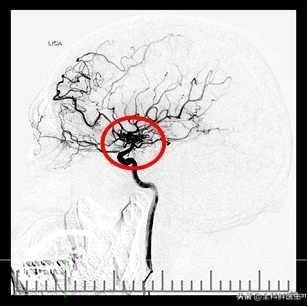

- die Ruptur eines intrakraniellen Aneurysmas ist ebenfalls eine der Hauptursachen für eine Hirnblutung.Bei vielen Patienten mit Hirnblutungen liegen angeborene intrakranielle arteriovenöse Fehlbildungen vor, wie z. B. das Vorhandensein von intrakraniellen Hämangiomen, die sich als Reaktion auf Blutdruckschwankungen langsam und schädlich ausdehnen und zu einer Ruptur und Blutung der Hämangiome neigen, sobald der intravaskuläre Druck die Spannung des Aneurysmas überschreitet.

- Die körperliche Untersuchung ermöglicht die frühzeitige Erkennung von Krankheiten wie intrakraniellen arteriellen Fehlbildungen und Aneurysmen.Werden intrakranielle Gefäßveränderungen festgestellt, können prophylaktische Behandlungen wie das Einsetzen von intrakraniellen Gefäßstents und die Tamponade von Hämangiomen mit Federspulen im Voraus durchgeführt werden.zur Verhinderung von Hirnblutungen.Die Untersuchung der intrakraniellen Blutgefäße ist jedoch relativ schwierig und erfordert eine CTA oder sogar eine Bildgebung des Schädels, die auch Auswirkungen auf den Körper haben kann.

- Intrakranielle vaskuläre Läsionen (endogen):Wenn Bluthochdruck eine exogene Ursache für intrakranielle Gefäßrupturen ist, sind intrakranielle Gefäßläsionen eine endogene Ursache für Hirnblutungen, zum BeispielVenöse Thrombose, vaskuläre Missbildungen, intrakranielle Mikroangiome, mikroskopische AtheroskleroseDiese führen zu einer pathologischen Schädigung der Blutgefäße, die bei Vorhandensein von exogenen Faktoren wie Bluthochdruck schließlich zu Blutungen führt.

3. vaskuläre Fehlbildung, Aneurysma: vaskuläre Fehlbildung, Aneurysma tritt Hirnblutung ist häufig bei jungen Menschen, ich habe gesehen, die jüngste ist erst zehn Jahre alt, und das ist nicht das erste Mal, dass sie einen Anfall hatte, jedes Mal, wenn der Angriff hat auf der Intensivstation aufgenommen werden. Es gab eine Assistenzärztin in den 30ern, die im Dienst einen Anfall hatte, der sich später als Hämangiom herausstellte. Diese Art von Krankheit kann in jungen Jahren durch eine MRT-Angiographie diagnostiziert werden, und nach der Diagnose kann sie in großen Krankenhäusern wie Peking und Shanghai chirurgisch behandelt werden, und die Kosten für die Behandlung sind auch eine große Summe Geld, aber sie sind unbedeutend im Vergleich zum Leben. Für diese Art von Patienten ist es auch wichtig, auf Ruhe zu achten, Müdigkeit zu vermeiden, anstrengende Übungen zu vermeiden und emotionale Aufregung zu vermeiden.